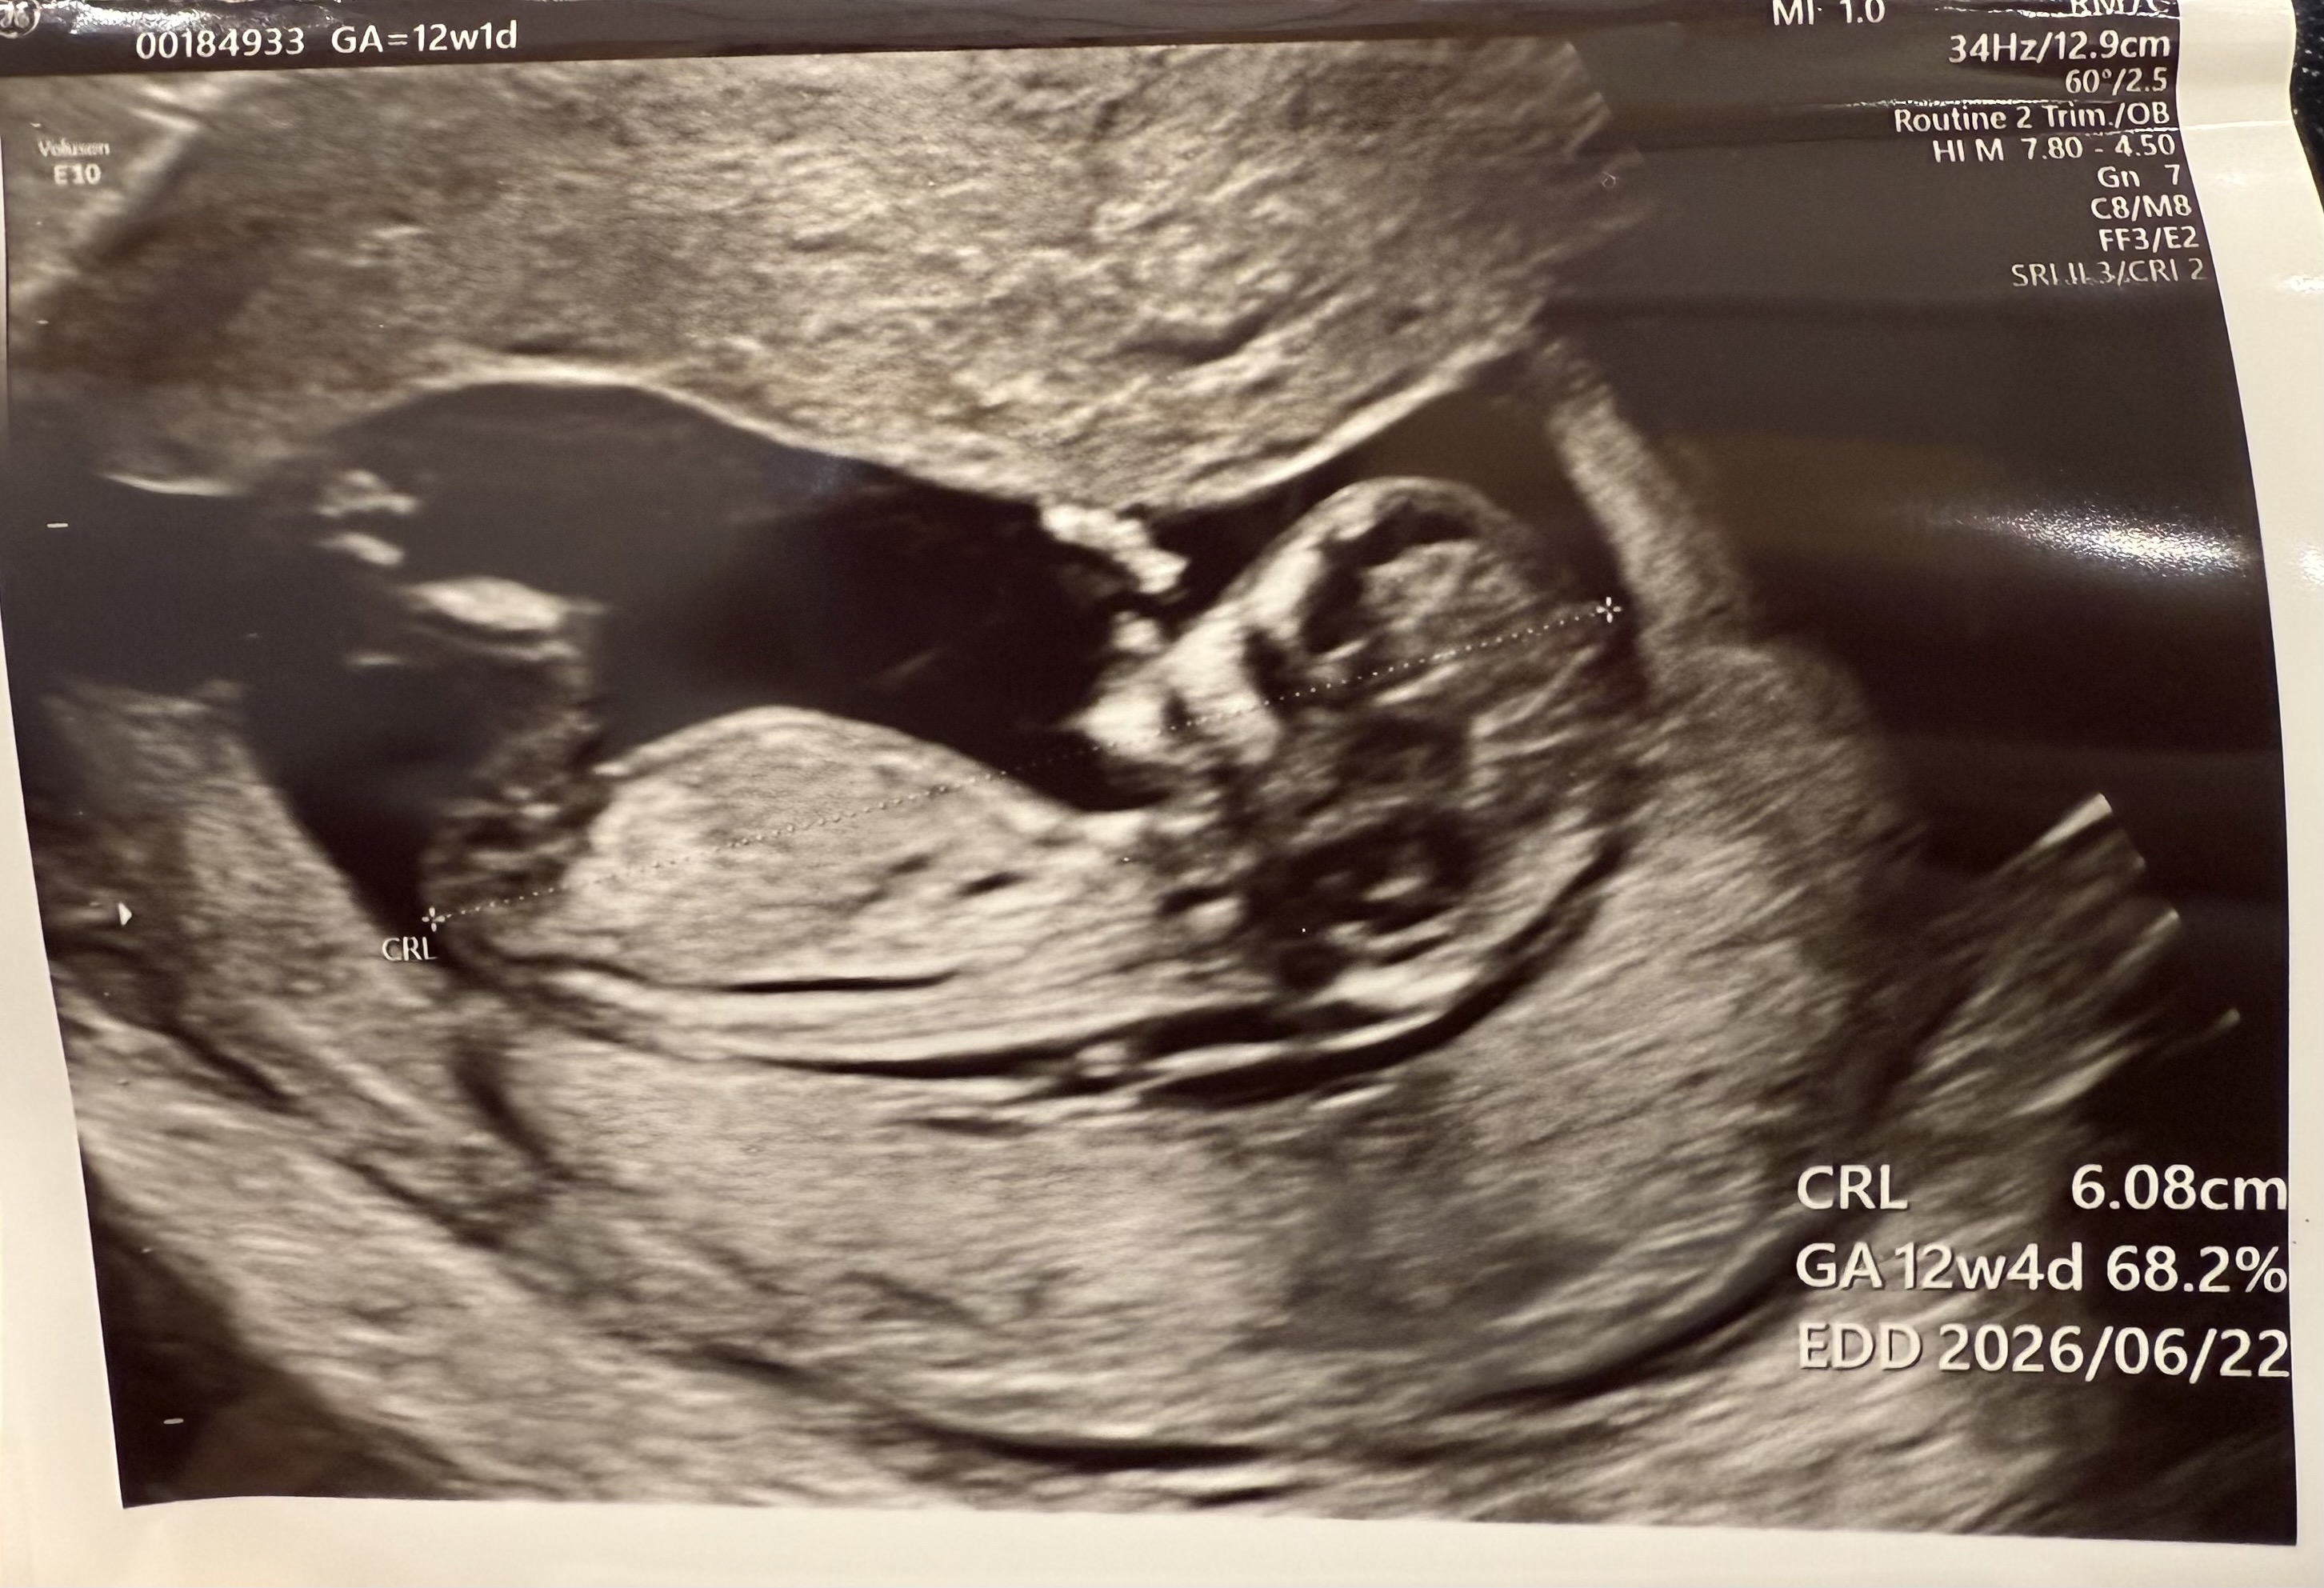

아기 각도법 봐주세욜~

12주 초음파 보고 왔는데 궁굼하네용 ☺️